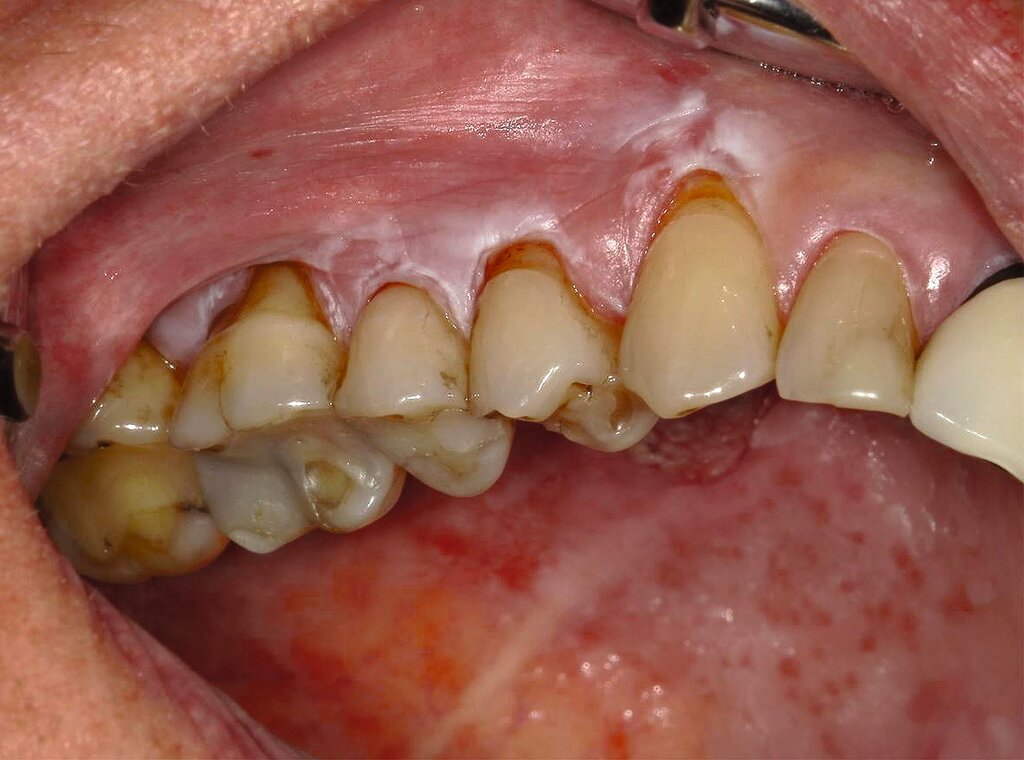

Typischerweise tritt die Leukoplakie bei Erwachsenen über 40 Jahren auf, häufiger bei Männern [Stolte und Dommisch, 2023]. Der wichtigste Risikofaktor ist der Tabakkonsum, sowohl Rauchen als auch Kautabak, gefolgt von regelmäßigem Alkoholkonsum, schlechter Mundhygiene und chronischen mechanischen Reizungen, beispielsweise durch scharfe Zahnkanten oder schlecht sitzende Prothesen. Auch Infektionen mit humanen Papillomaviren können eine Rolle spielen und sind derzeit Gegenstand der Forschung [Mello et al., 2018; Mishra et al., 2005; Feller und Lemmer, 2012]. Einige Leukoplakien treten auch bei lebenslangen Nichtrauchern ohne erkennbare Ursache auf; in solchen Fällen spricht man von einer idiopathischen Leukoplakie. Bei diesen Personen wird ein erhöhtes Risiko für die Entstehung oraler Plattenepithelkarzinome vermutet [Stolte und Dommisch, 2023; Napier und Speight, 2008]. Zu den wichtigsten Differenzialdiagnosen zählen die orale Haarleukoplakie, der orale Lichen planus, Candidiasis und Morsicatio buccarum [Kämmerer et al., 2017].

Die Leukoplakie äußert sich in Form von weißlichen Flecken oder Plaques auf der Mundschleimhaut, die nicht abgewischt werden können. Sie sind in der Regel schmerzlos, können aber durch ihre Beschaffenheit – meist rau oder leicht erhaben – auffallen. Am häufigsten sind sie an der Wangeninnenseite, am Alveolarfortsatz, an der Zunge, am Mundboden oder an den Lippen zu finden [Kämmerer et al., 2017; Speight et al., 2018]. Je nach Aussehen und histologischer Beurteilung unterscheidet man die homogene Leukoplakie von der inhomogenen Leukoplakie. Die homogene Leukoplakie zeigt sich als gleichmäßig weißer, glatter oder leicht rauer Fleck (Abbildung 1). Ihr Risiko, bösartig zu entarten, gilt als gering. Inhomogene Leukoplakien haben im Gegensatz dazu ein erhöhtes Entartungsrisiko und lassen sich in weitere Formen unterteilen: die gesprenkelte Form, auch als Erythroplakie bezeichnet (eine Mischung aus weißen und roten Arealen, wobei der weiße Anteil überwiegt), die noduläre Form (kleine, polypenartige Vorwölbungen mit rundlichen, roten oder weißen Erhebungen) und die verruköse Form (gekennzeichnet durch eine gefurchte oder warzenartige Oberfläche) (Abbildungen 2 und 3) [Kämmerer et al., 2017; Warnakulasuriya et al., 2016].

Therapeutisch steht, wie bereits erwähnt, die konsequente Beseitigung potenzieller Noxen im Vordergrund – insbesondere die Einstellung des Tabakkonsums sowie gegebenenfalls die Anpassung schlechtsitzender Prothesen oder scharfer Zahnkanten. Bei unauffälligem zytologischem Befund und fehlender Symptomatik ist ein konservatives Vorgehen mit regelmäßiger klinischer Kontrolle gerechtfertigt, wobei ein Intervall von sechs Monaten ausreichend erscheint [van der Wahl, 2009; Kunkel et al., 2011]. Eine chirurgische Therapie ist in diesen Fällen in der Regel nicht erforderlich. Ebenfalls kann auf eine Biopsie verzichtet werden, wenn nach Ausschalten der Risikofaktoren ein Rückgang der Läsion erkennbar wird (Abbildungen 5 und 6) [Kunkel et al., 2011].